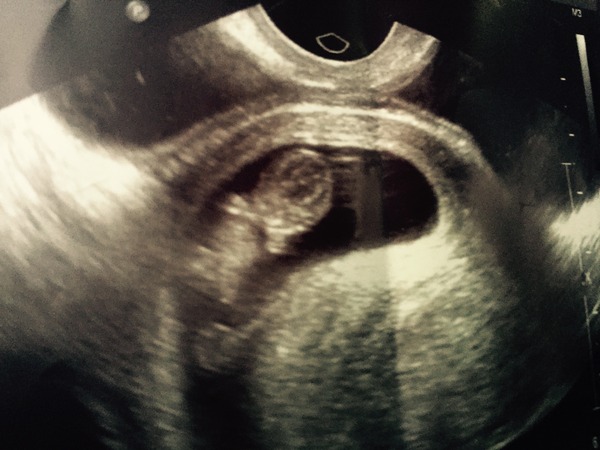

Thanks for the wishes Gnomette. Had the scan and all is well! Right on schedule at 9weeks 2 days. And best thing is - We have arms and legs!!

Lovely scan picture nehagarg. So exciting. Can't wait to have mind in 3 weeks time